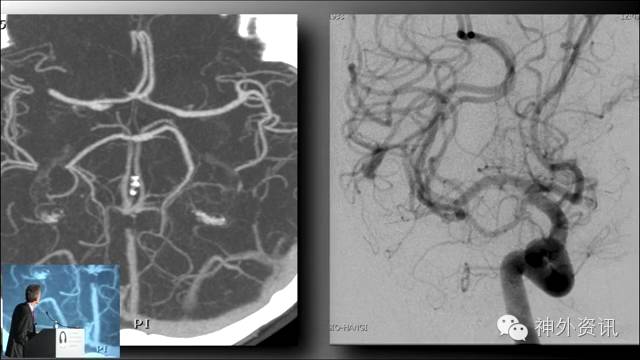

Michael T. Lawton,巴洛神经科学研究所(BNI)主席,精于各种脑血管疾病的治疗,已累及外科治疗4400余例颅内动脉瘤和700余例AVM,发表论文270余篇,参编书籍40余部,著有《Seven Aneurysms: Tenets and Techniques for Clipping》。